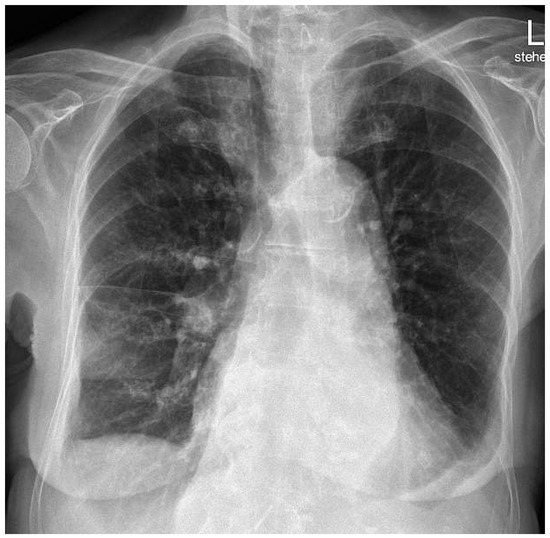

Case report. A 63-year-old hypertensive male presented with atypical chest discomfort and breathlessness on exertion [...]